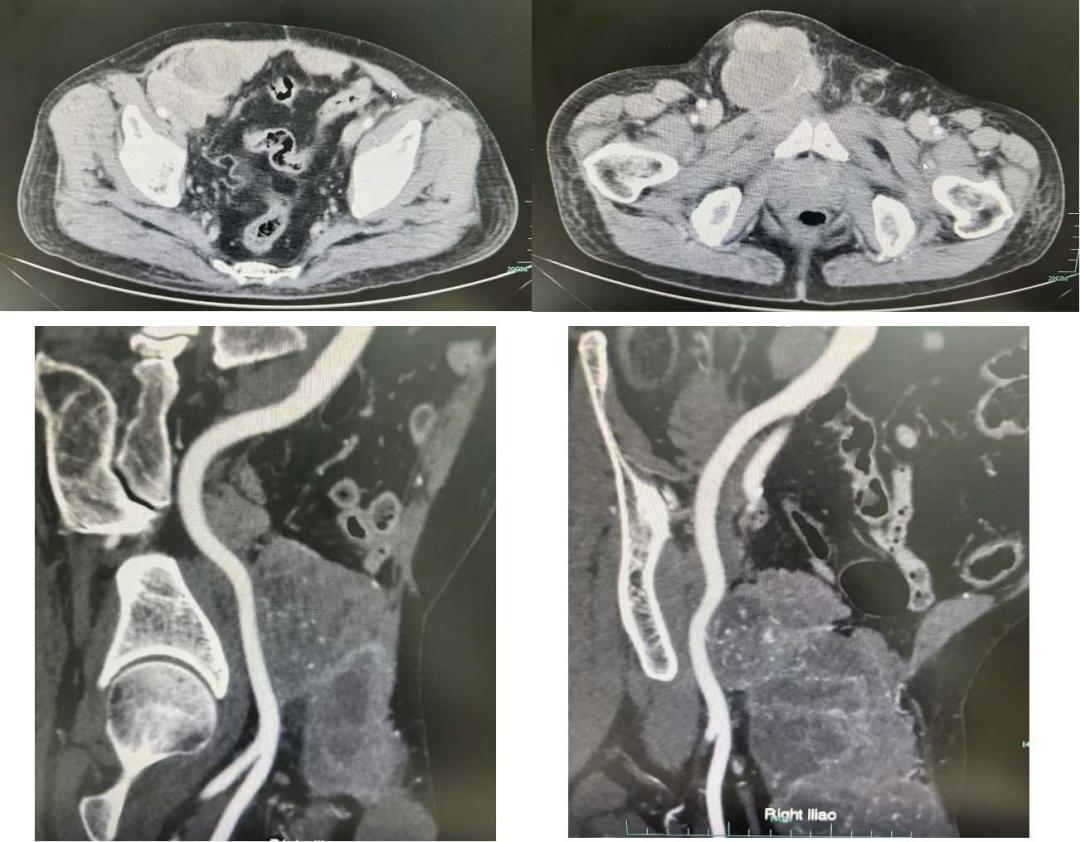

张伯因对手术可能带来的身体负担感到忧虑,故推迟了治疗进程。其肿块已膨胀至鸵鸟蛋般体积,对输尿管、阴囊、右侧髂血管及腹股沟管造成了严重影响。经当地医院评估,张伯被认定无法承受手术,并被建议转院至头部三甲医院接受治疗。此建议使得张伯及其家人陷入了极大的绝望与困惑之中。